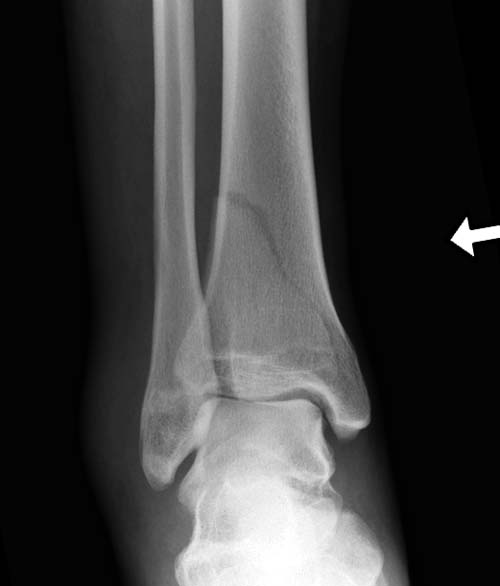

Второй случай в результате скоростной травмы, кроме пилона, вовлечение

других органов! Отек при поступлении и открытый перелом на другой

стороне. В таких случаях нет смысла спешить, и временный наружный

фиксатор на несколько дней. После спадения отека фиксация

передне-наружной пластиной.  Реабилитация - ранние движения, без

нагрузки.